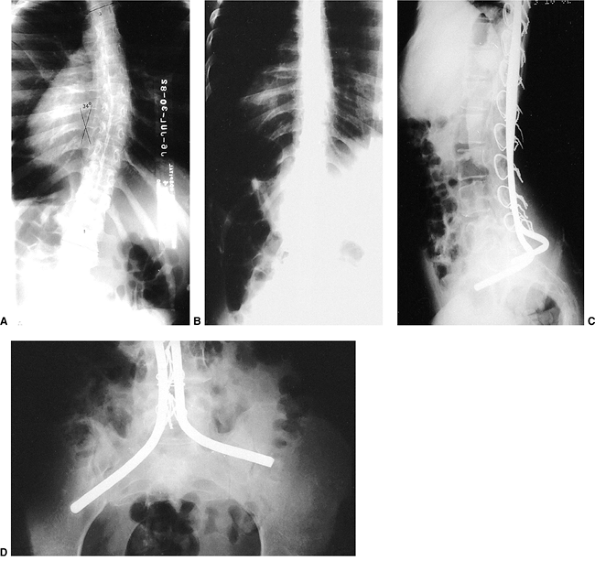

used (106,107,111,116). These allow sufficient fixation so that postoperative immobilization is not necessary (Fig. 17.2). Fixation to the pelvis is achieved using the Galveston or other techniques (103,106,110,111,112,113,114,115,116,117).

Figure 17.2 A:

An 11-year-old boy with Duchenne muscular dystrophy with a rapidly progressive right thoracolumbar scoliosis and decreasing sitting balance. He uses his hands to maintain sitting balance. B: Side view shows an associated mild kyphotic deformity. C: Preoperative sitting posteroanterior radiograph demonstrates a long, sweeping, 48-degree thoracolumbar curve between T-11 and L-5. Six months earlier, no clinical or radiographic deformity was evident. D: Postoperatively, an immediate improvement in spinal alignment and sitting balance is noted. E: Side view demonstrates correction of the associated kyphosis. F: Postoperative sitting radiograph after posterior spinal fusion and Luque rod instrumentation from T-4 to the sacrum. The Galveston technique, with insertion of the Luque rod into the wing of the ilium, was used for pelvic fixation. Almost complete correction of his spinal deformity was achieved. G: Postoperative lateral radiograph shows improved sagittal alignment. |